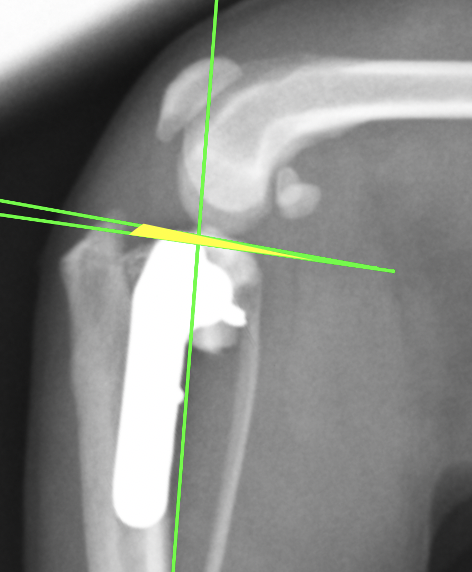

術後のレントゲン画像です。先程までずれていた矢印が合っているのがわかります。

またTPAと呼ばれる角度も小さくなっているのが確認できます(6°)。6°前後が理想的と言われています。